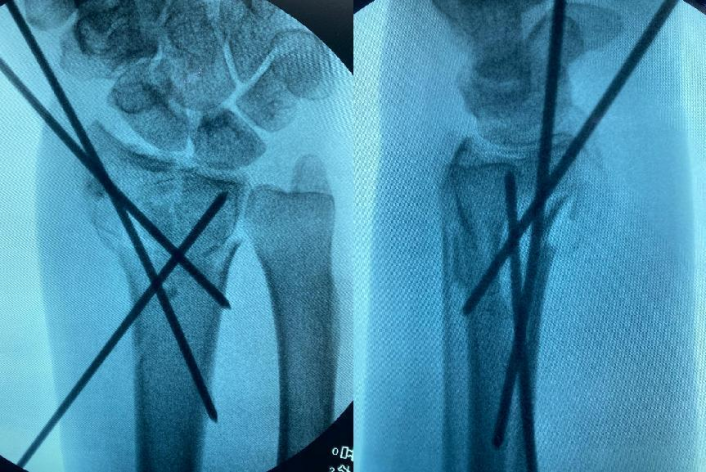

(▲X光片清晰可见艾先生左桡骨远端粉碎性骨折。)

刻不容缓,医院当天傍晚就为艾先生安排了手术。因其伤势,医生团队决定行左尺桡骨骨折复位内固定术和石膏外固定术。术中,医生首先行牵引,将桡骨骨折端用手法复位后,在C臂机透视下见桡骨骨折断端对位对线良好,便从远端桡侧至近端尺侧,用电钻分别钻入一枚直径2.0mm的金属骨针固定,再经C臂机透视下确认桡骨骨折断端对位对线良好,内固定在位。手术顺利,整个过程仅持续一小时。

“一般治疗桡骨远端骨折是通过切开皮肤复位上钢板,而我院是采取闭合复位打克氏针固定,即不用切开皮肤,属于微创手术,让患者的治疗感受更好,恢复更快,同时对复位技术要求难度也大大增加。”任俊成医生说道。

(▲C臂机透视下经皮置入克氏针固定骨折端。)